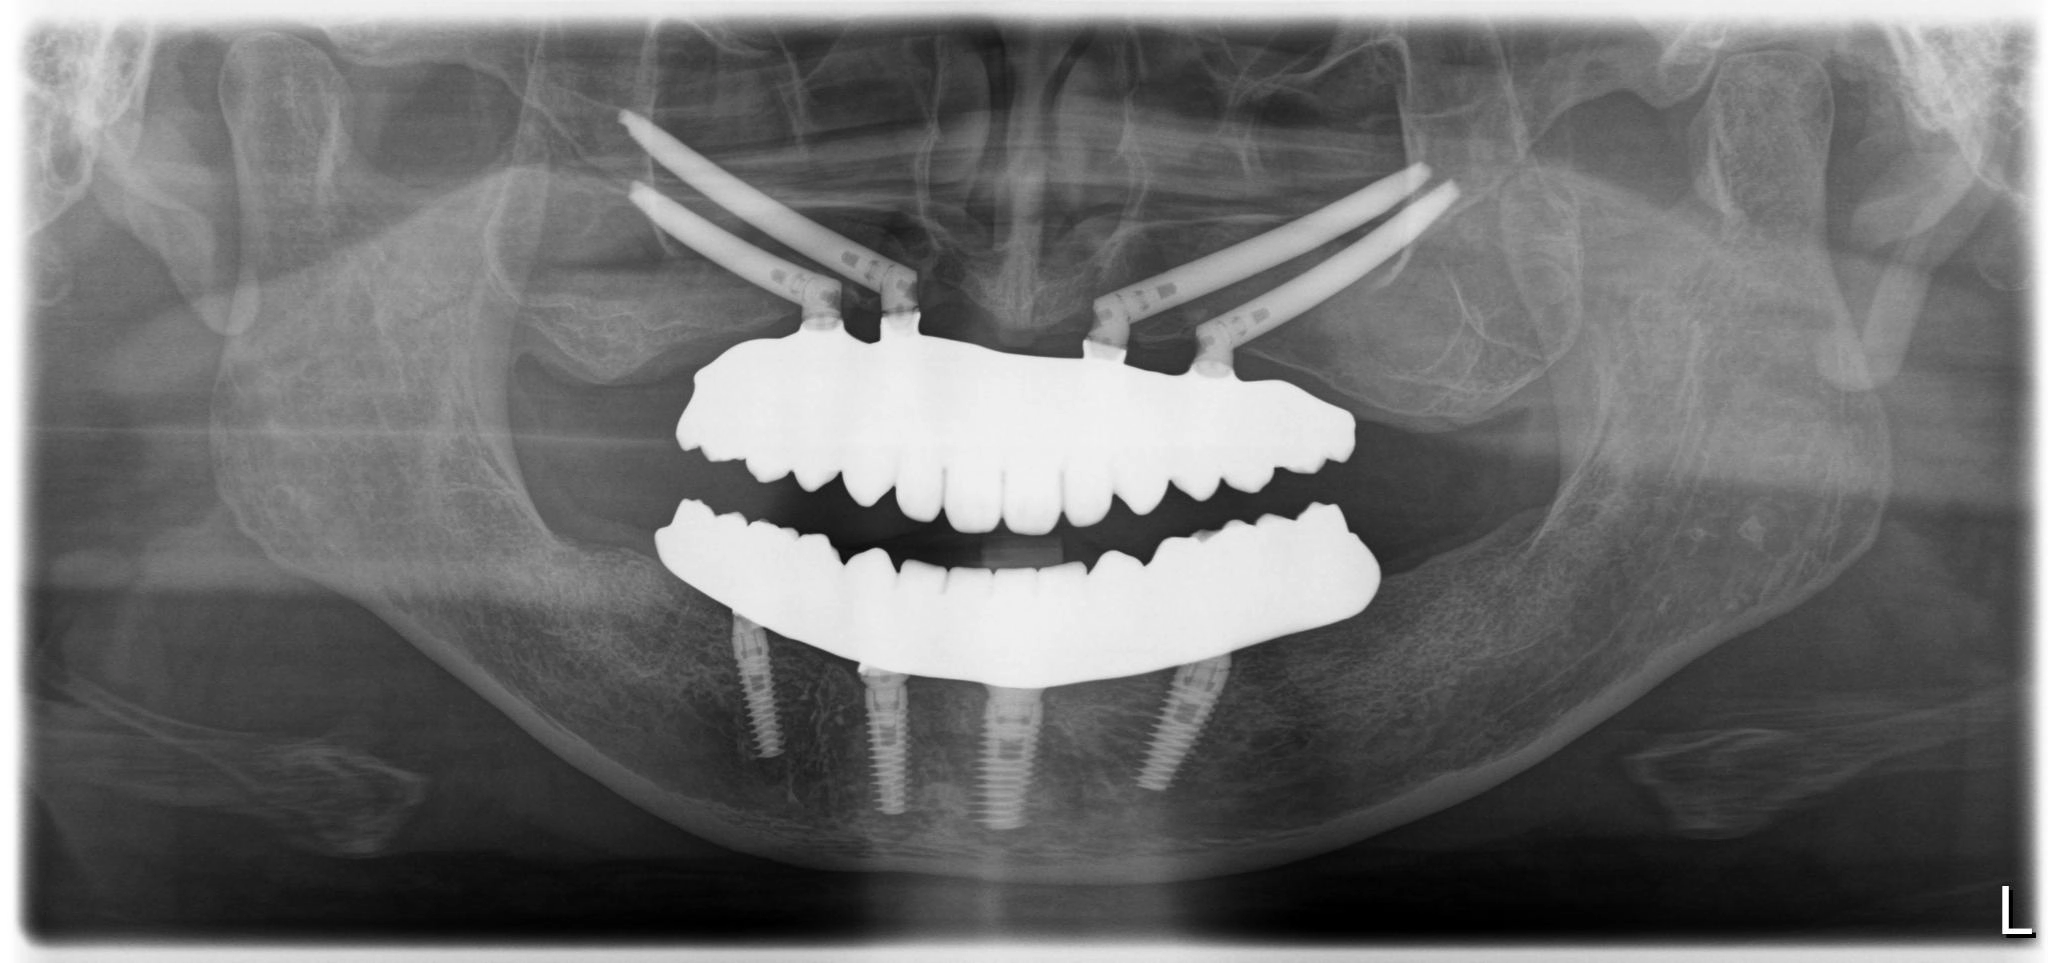

内容 :上下顎オールオン4ザイゴマ4

費用 :5,500,000円

※モニター価格

期間 :半年

リスク:出血・腫れ・痺れ・痛み